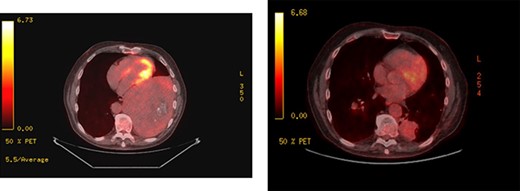

Upon re-presentation in 2019, workup included brain magnetic resonance imaging (MRI), positron emission tomography (PET) scan and re-biopsy. Brain imaging revealed a 6 mm solitary right parietal brain metastasis (Fig. 3). On PET scan, the tumour exhibited mild FDG uptake, with the SUV max of 2.9 (Fig. 4). There was no evidence of nodal or distant metastatic disease. Biopsy again was consistent with SFT. The patient was reviewed at Multidisciplinary Thoracic Tumour Board Rounds. Considering the large size and compressive effects of the pleural-based tumour, combined with the small size and asymptomatic nature of the brain lesion, it was determined that the optimal approach would be surgical resection of the left-sided pleural SFT and active surveillance of the brain metastasis. The patient underwent complete en bloc resection of the tumour via left thoracotomy including the eighth rib, partial pleurectomy and a left lower lobe wedge resection to achieve an R0 resection (Fig. 5).

PET scans; large left-sided pleural-based tumour exhibits mild FDG uptake, with the SUV max of 2.9 (left); recurrent disease at the pulmonary resection margin along with contralateral pulmonary metastases demonstrated (right).